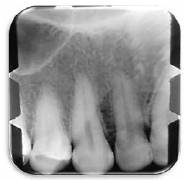

Se solicitó radiografía periapical bisectal de dientes 1.1 al 1.4 (Figura 3) y una radiografía oclusal de la zona (Figura 4). No se observaron alteraciones óseas.